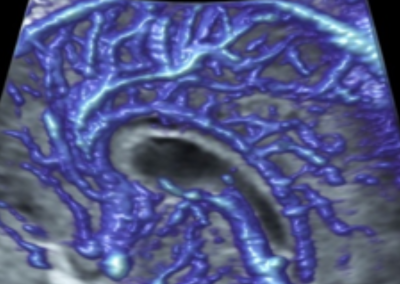

L’Université Paris Cité franchit une nouvelle étape dans le domaine de l’imagerie médicale anténatale avec l’acquisition d’un système d’Imagerie par Résonance Magnétique (IRM) 1,5T ARTIST™ de GE HealthCare. Cet équipement de pointe renforce les capacités de la Plateforme LUMIERE à l’hôpital Necker-Enfants malades, plateforme intégrée de soins, de recherche clinique et d’enseignement en imagerie médicale de la femme enceinte, du fœtus et du placenta.

L’acquisition de cette nouvelle IRM s’inscrit dans le cadre du protocole de recherche « LUMIERE SUR LE FETUS », dont les objectifs sont d’améliorer la prise en charge des pathologies anténatales, d’affiner leur pronostic et de contribuer à la réduction de la morbidité et de la mortalité à court, moyen et long terme. Cette acquisition a été rendue possible grâce au don exceptionnel de la Fondation LUMIERE d’un montant de 250k euros ainsi qu’au soutien de l’Université Paris Cité à hauteur de 670k euros.

Depuis 2020, la Plateforme LUMIERE offre aux femmes enceintes volontaires, entre 16 et 36 semaines d’aménorrhée et suivies à l’hôpital Necker-Enfants malades, la possibilité de participer activement à l’avancée de la recherche en médecine fœtale, tout en bénéficiant d’une IRM fœtale au cours de leur grossesse, réalisée dans un cadre sécurisé et encadré.

L’inclusion de ces patientes, depuis leur accueil jusqu’à la réalisation des examens d’imagerie, puis l’analyse des images et l’interprétation des résultats par des équipes expertes, enrichit une base de données structurée, unique au monde, au service de la recherche et de l’innovation en imagerie anténatale et en médecine fœtale.